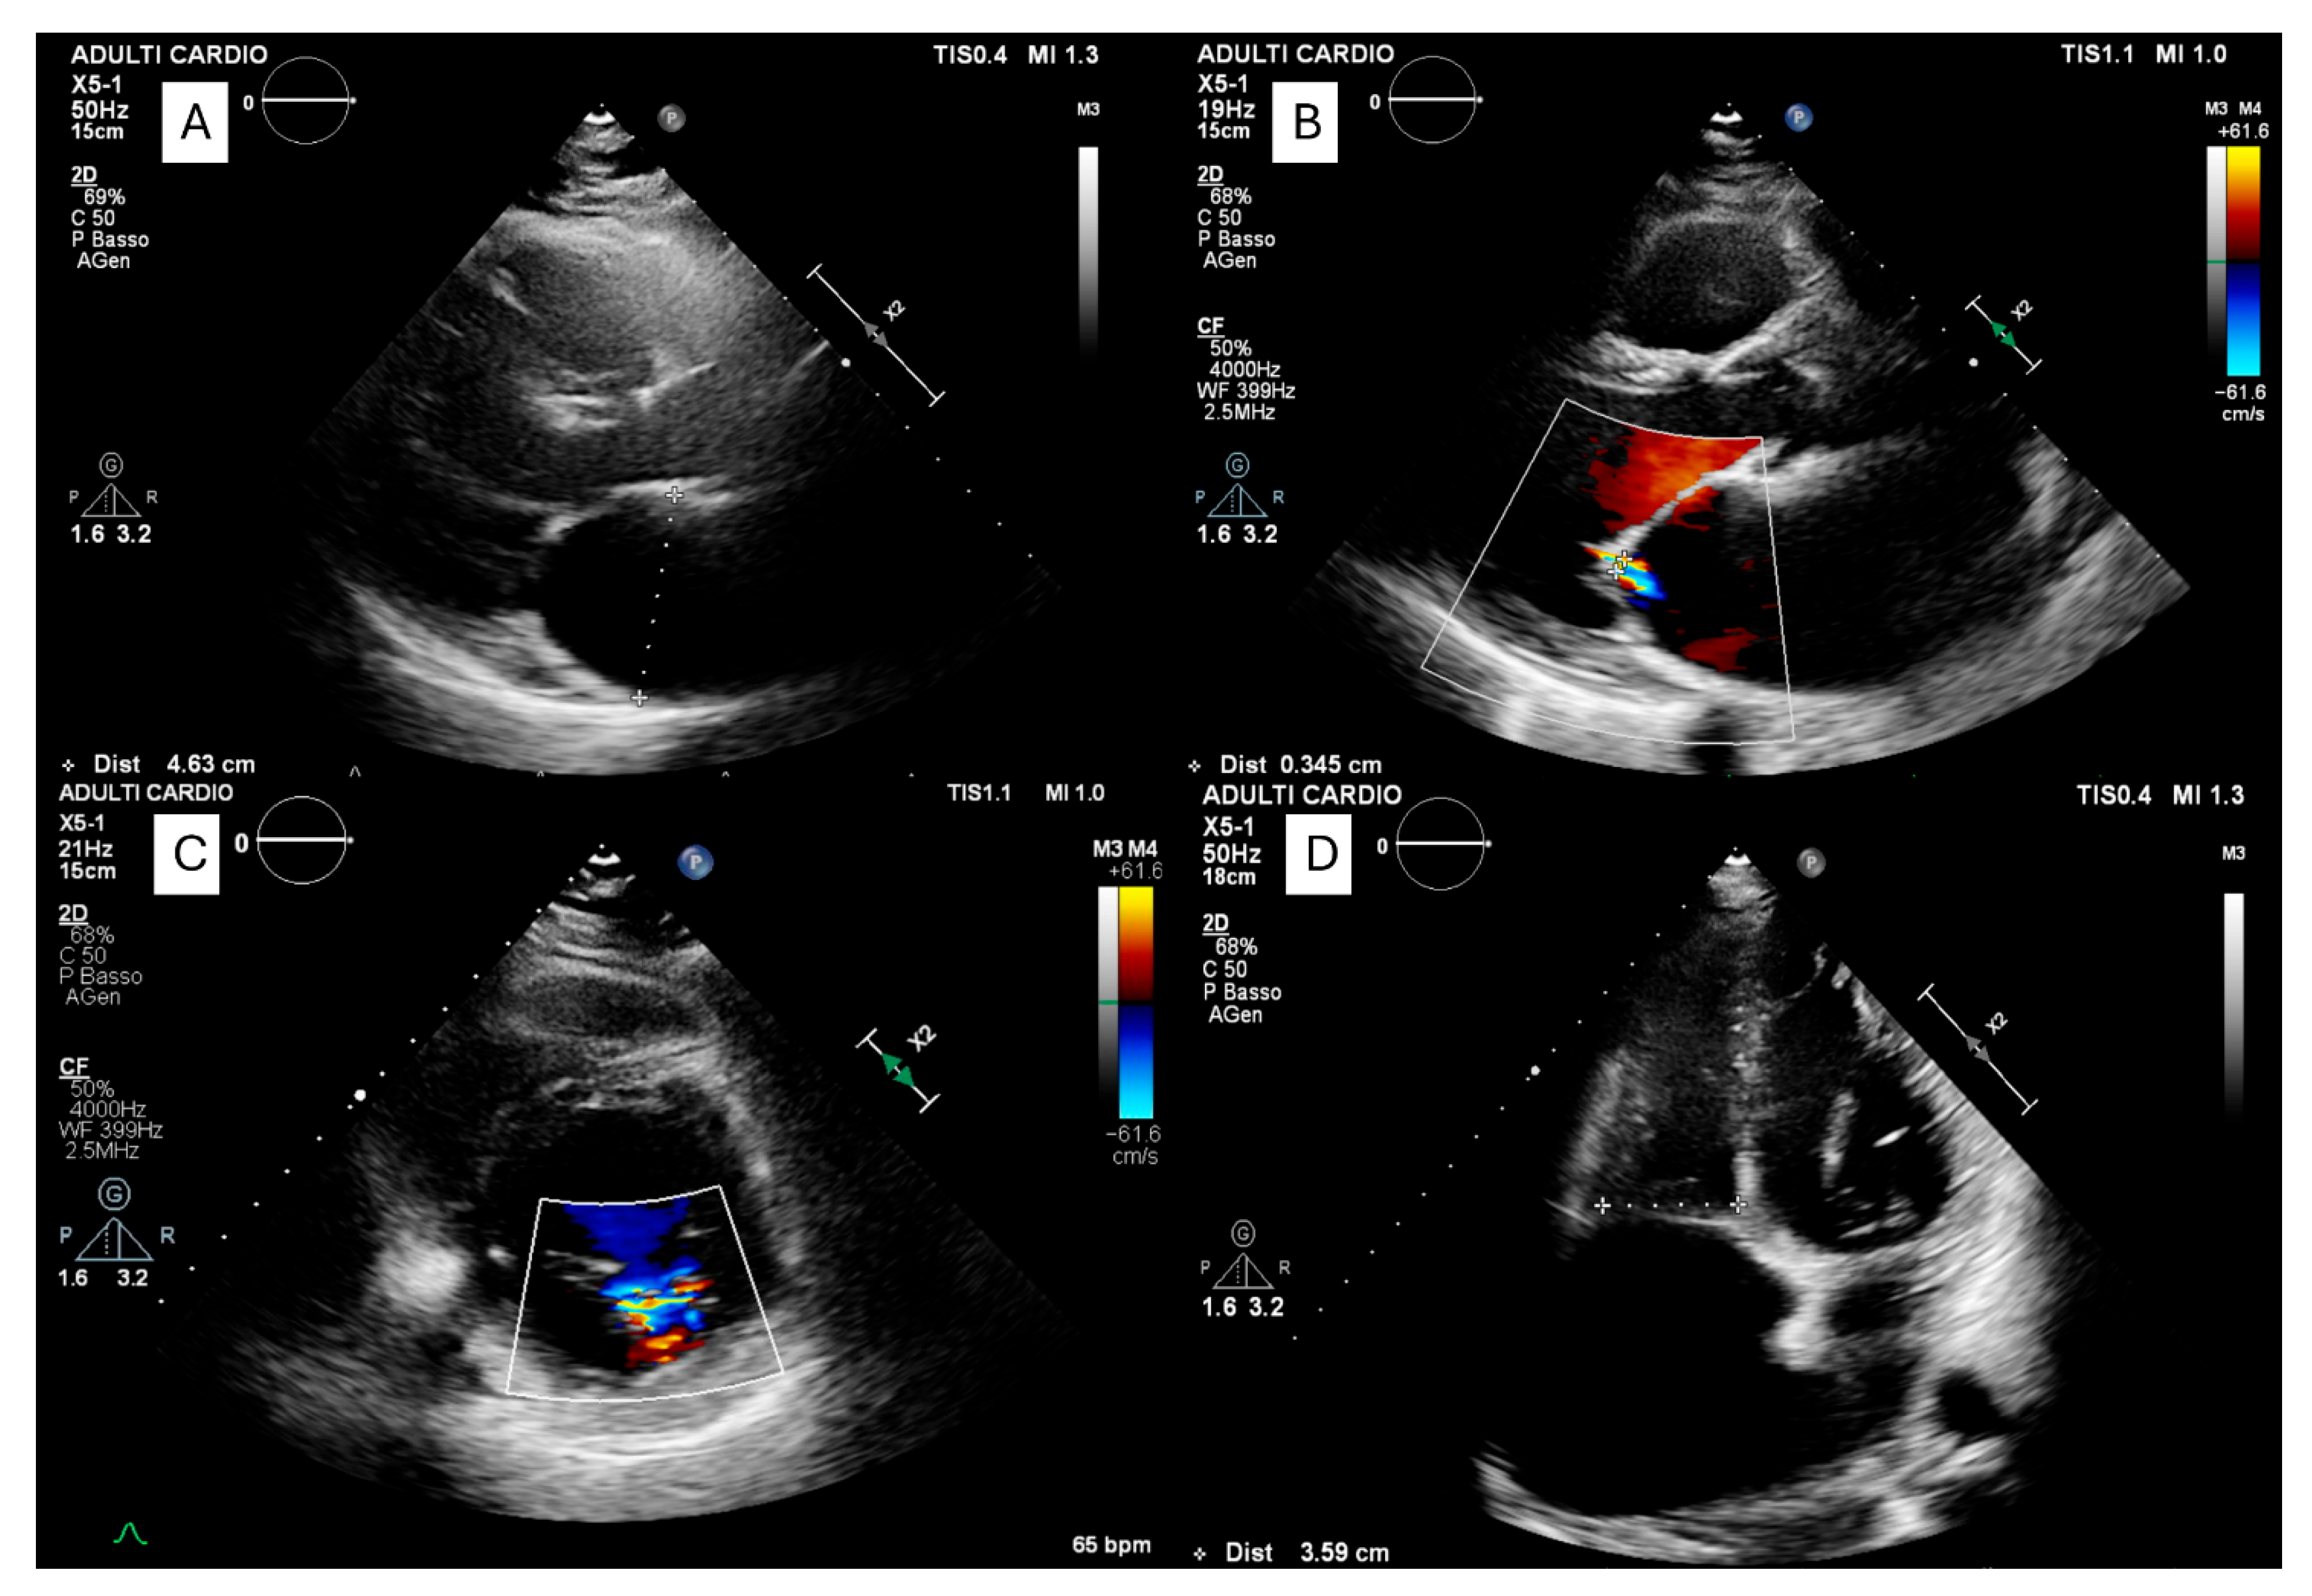

- Forleo, C.; Dicorato, M.M.; Carella, M.C.; Basile, P.; Dentamaro, I.; Santobuono, V.E.; Guaricci, A.I.; Resta, N.; Ciccone, M.M.; Arbustini, E. NPPA-Associated Atrial Dilated Cardiomyopathy: Genotypic and Phenotypic Insights From an Ultrarare Inherited Disorder. JACC Case Rep. 2025, 30, 105141. [Google Scholar] [CrossRef] [PubMed]